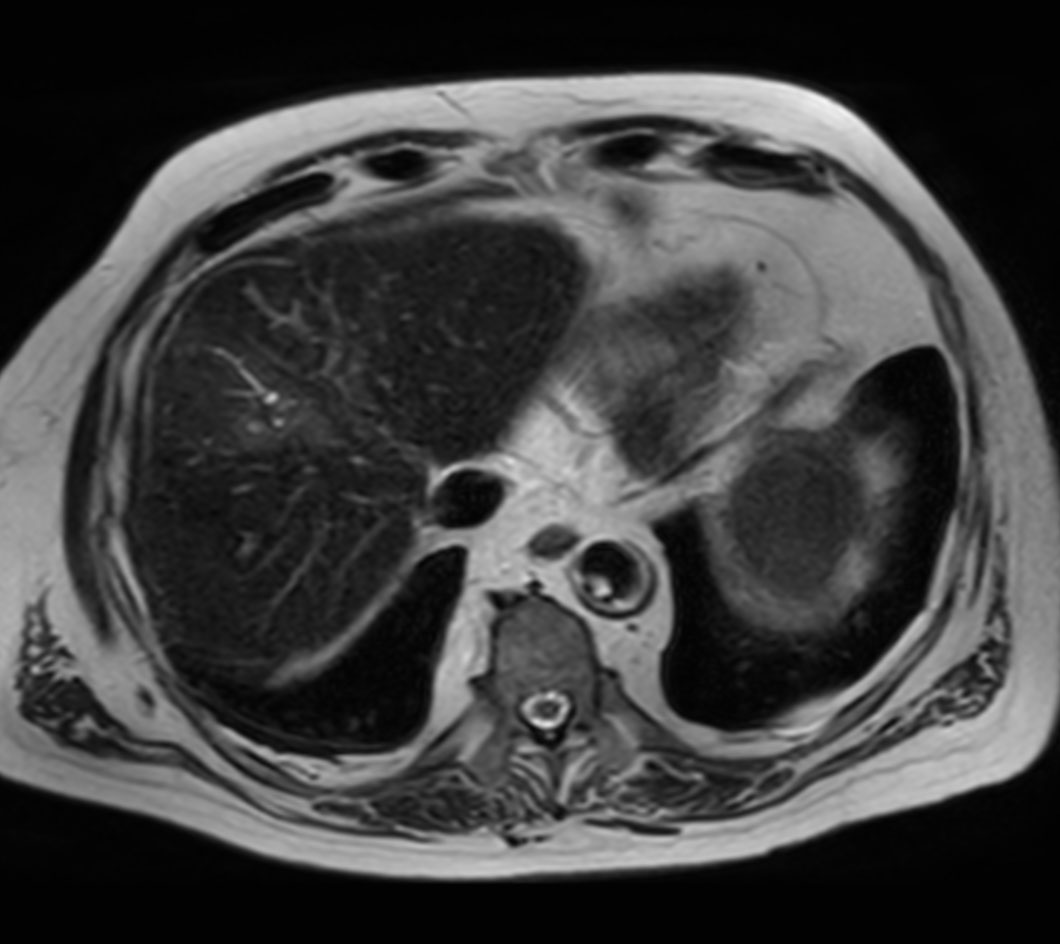

Axial T2w SPAIR - MultiVane XD